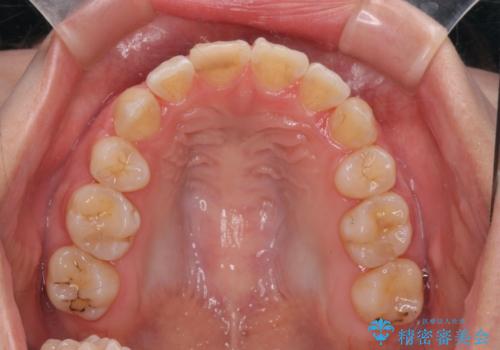

綺麗な歯並びを手に入れられたと同時に、口元もスッキリし、仕上がりに満足いただくことができました。